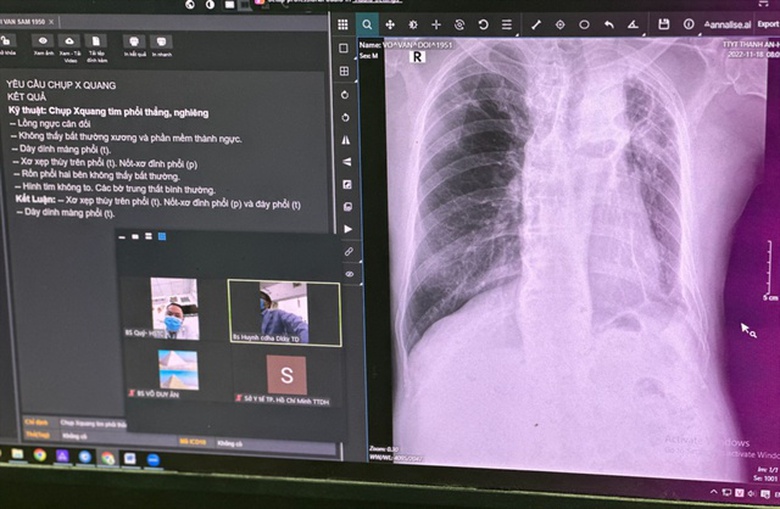

Để khám và kiểm tra sức khoẻ của một người bệnh ho ra máu, chỉ vài động tác chạm tay lên màn hình của máy X-quang, BS. Tỷ đã tự tin đọc các thương tổn trên phim X-quang là xẹp phân thuỳ phổi P, dày màng phổi và tràn dịch màng phổi T.

Nhờ ứng dụng AI được tích hợp trên máy X-quang kỹ thuật số và kết nối hệ thống PACs, các thương tổn trên X- quang phổi nhanh chóng được liệt kê trên màn hình; đồng thời, các hình ảnh X-quang phổi vừa chụp được dễ dàng chuyển đi để xin ý kiến tư vấn của các bác sĩ chuyên khoa tại Bệnh viện Đa khoa khu vực Thủ Đức.

Chưa tới 15 phút, sau khi xin ý kiến của các bác sĩ tuyến trên, bác sĩ trẻ tại trạm y tế này đã có được chẩn đoán chính xác và kế hoạch điều trị rõ ràng cho người bệnh.

Đây là trạm y tế đầu tiên của cả nước đã ứng dụng thành công trí tuệ nhân tạo trong chẩn đoán hình ảnh X-quang phổi, thông qua hệ thống PACS và ứng dụng telemedicine.